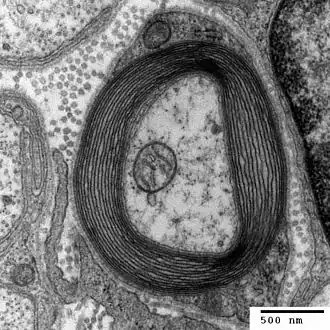

Another hypothesis is that copper deficiency myelopathy is caused by disruptions in the methylation cycle.[10] The methylation cycle causes a transfer of a methyl group (-CH3) from methyltetrahydrofolate to a range of macromolecules by the suspected copper-dependent enzyme methionine synthase.[10] This cycle is able to produce purines, which are a component of DNA nucleotide bases, and also myelin proteins.[10] The spinal cord is surrounded by a layer of protective protein coating called myelin (see figure). When this methionine synthase enzyme is disrupted, the methylation decreases and myelination of the spinal cord is impaired. This cycle ultimately causes myelopathy.[10]